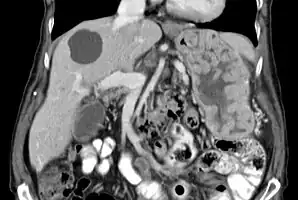

Ménétrier's disease

CT abdomen, coronal section, showing characteristic large rugal folds in the stomach. A cyst is also seen in the liver